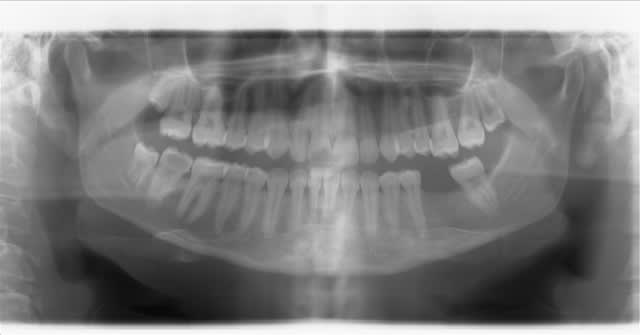

En pièce jointe la dent qui m'a fait posé cette question(radio pré-op) On se rapproche quand même bien du cas de Céramik, pour ne pas dire que c'est le même...

--